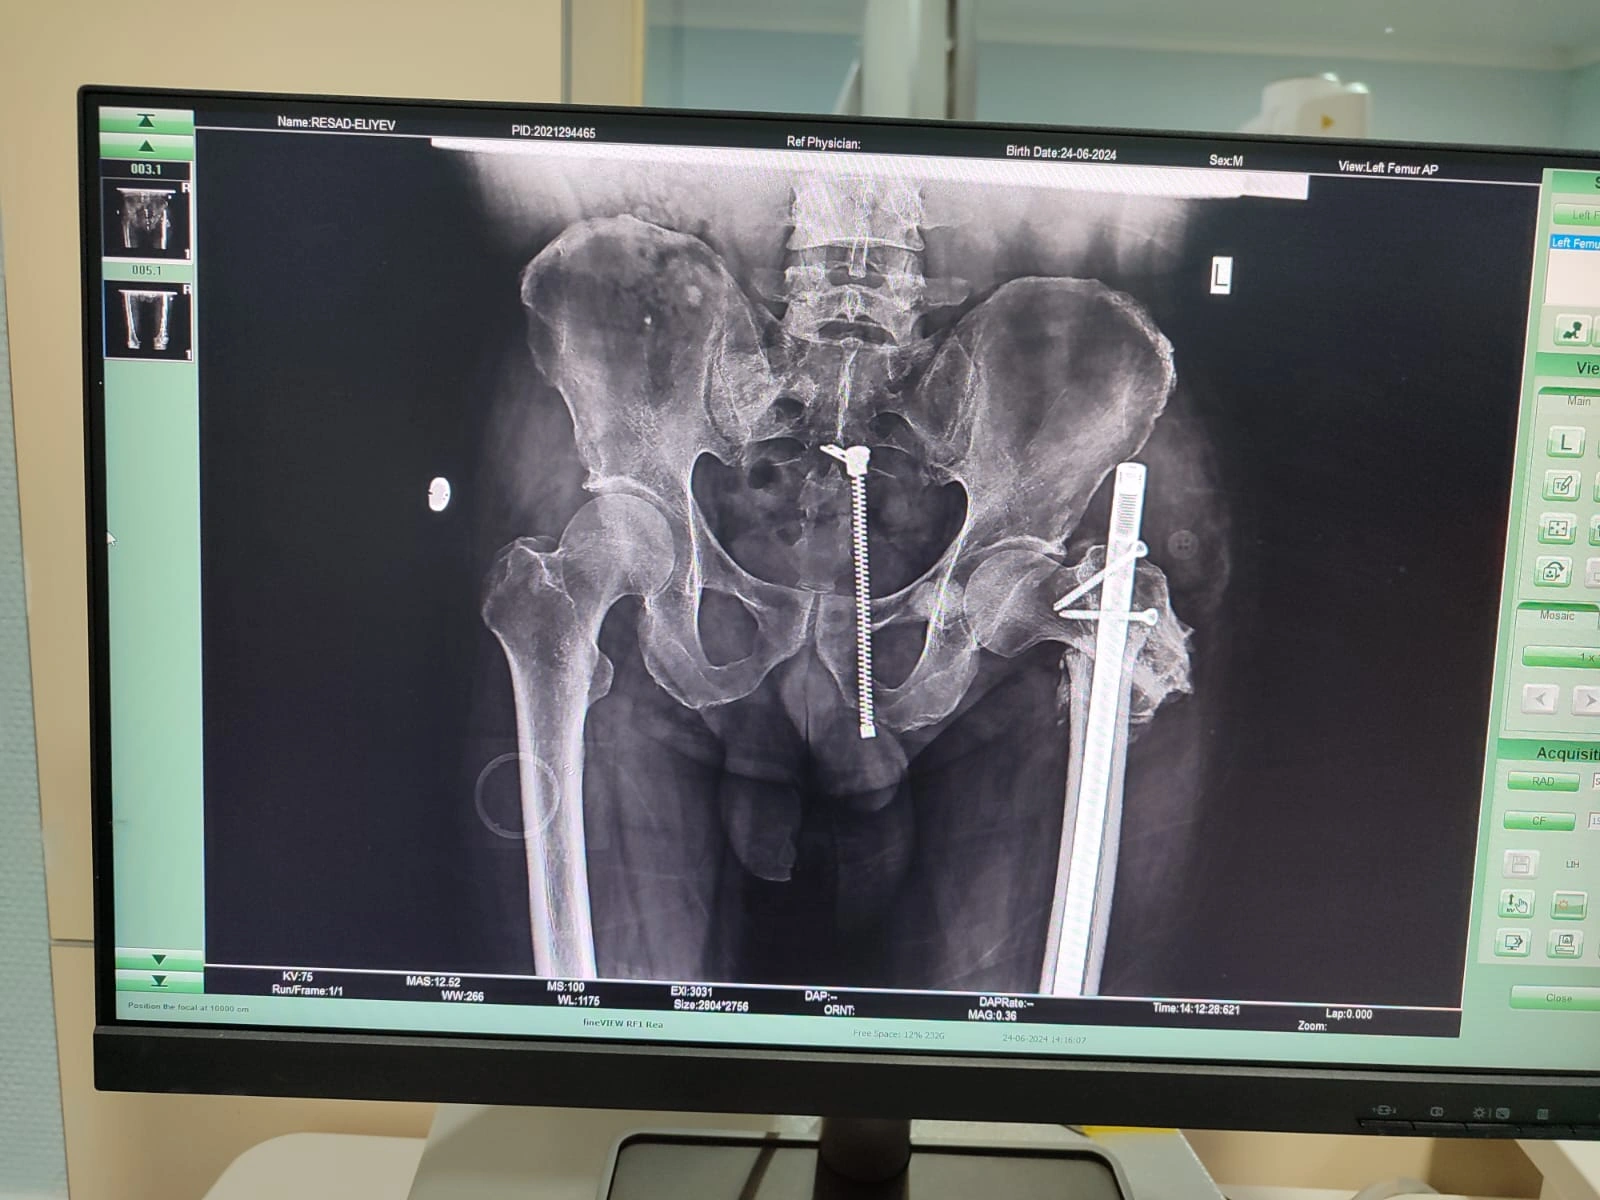

Bununla yanaşı, R. Əliyev daha ağır problemlə üzləşib. Onkoloji xəstə bir müddət öncə yıxılması nəticəsində oma sümüyü qırılıb. Həkimlər ona problemin aradan qaldırılması üçün endoprotez əməliyyatını təcili və vacib sayıb. Bu əməliyyatın icrası üçün isə 35 min dollar lazımdır. Anadolu Sağlık Mərkəzininin həkimləri bildiriblər ki, əməliyyatın təcili icrası vacibdir. Onkoloji xəstəlikdən uzunmüddətli müalicədə olduğundan isə ailənin bu məbləği qarşılamağa heç bir imkanı yoxdur.